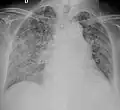

| Chest X ray showing miliary tuberculosis | |

Miliary tuberculosis is a form of tuberculosis that is characterized by a wide dissemination into the human body and by the tiny size of the lesions (1–5 mm). Its name comes from a distinctive pattern seen on a chest radiograph of many tiny spots distributed throughout the lung fields with the appearance similar to millet seeds—thus the term "miliary" tuberculosis. Miliary TB may infect any number of organs, including the lungs, liver, and spleen.[2]